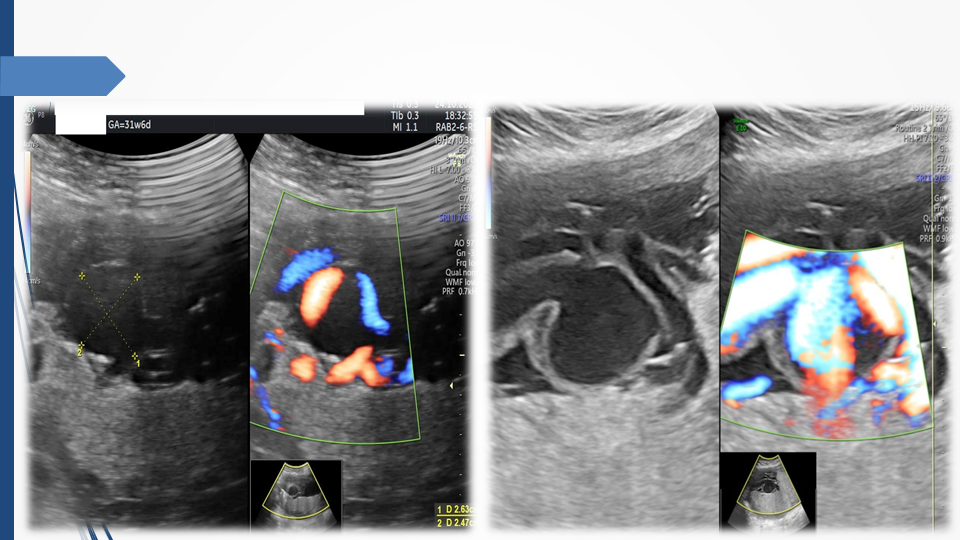

Tầm soát chủ động bất thường dây rốn và tuần hoàn thai để giảm thiểu nguy cơ thai lưu đột ngột - Báo cáo loạt ca hiếm gặp và khuyến nghị thực hành